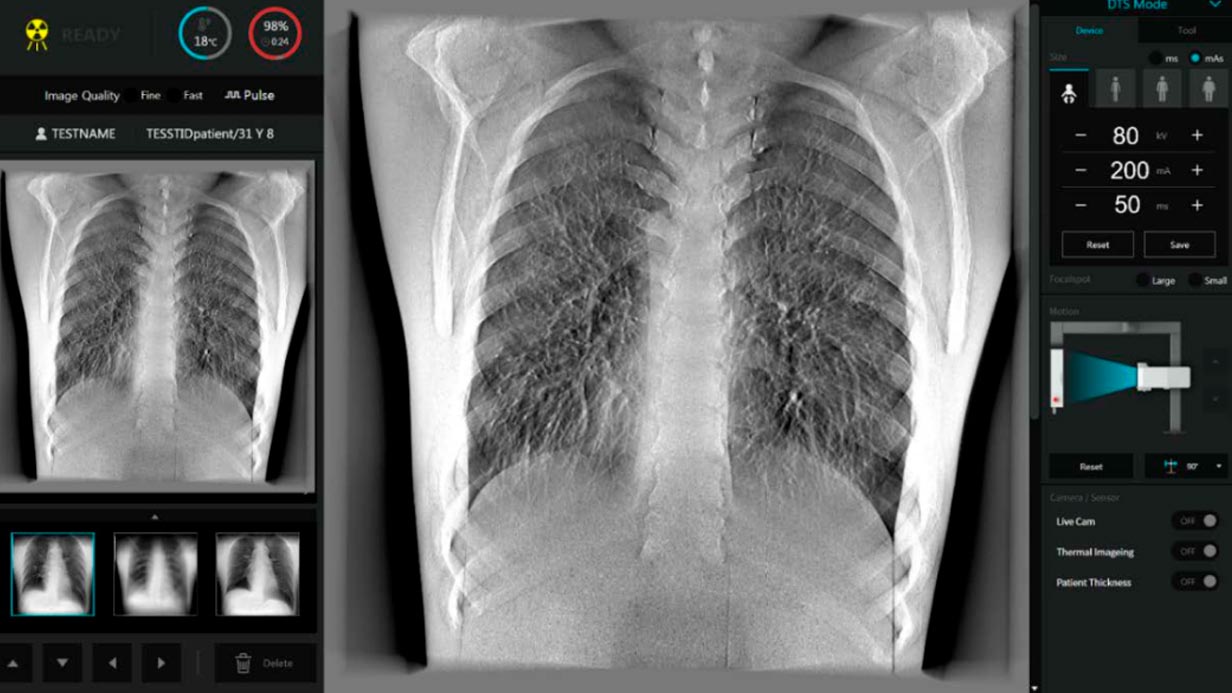

- Tomosíntesis

- Fluoroscopía

- Radiografía

Interfase Digital

- Guía de posición

- Pantalla Infográfica

Fluoroscopía

- En tiempo real sin arco en C

- Gran campo de visión de 17″ x 17″

- Velocidades de cuadros hasta 30 FPS

- Procesamiento de imágenes en tiempo real basado en GPU

- Procesamiento de imágenes avanzado